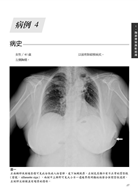

病例3 壞死性筋膜炎(Necrotizing fasciitis) 13